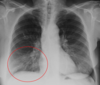

Tromboembolia pulmonar

Oclusión de arterias pulmonares por trombo de origen venoso

Rx para TEP

* Atelectasias basales * Elevación del diafragma * Joroba de Hampton * Signo de Westmark (aumento de lucidez = se ve más negro) * Dilatación de arteria pulmonar

¿Qué es el signo de la joroba de Hampton?

Opacificación pleural en "domo" Secundario a infarto y hemorragia

Joroba de Hampton = TEP

¿Qué es el signo de westermark?

Hiperlucencia periférica (por oligoemia)

Signo de Westermark = TEP

Dilatación de arteria pulmonar = TEP